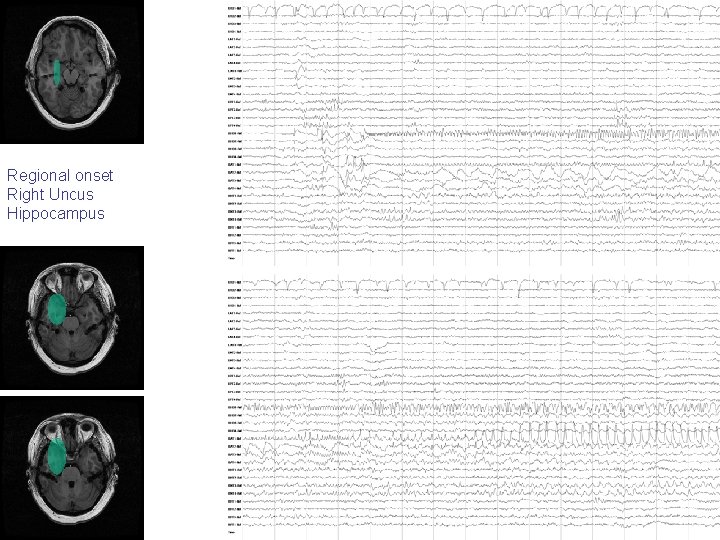

Regional onset Right Uncus Hippocampus